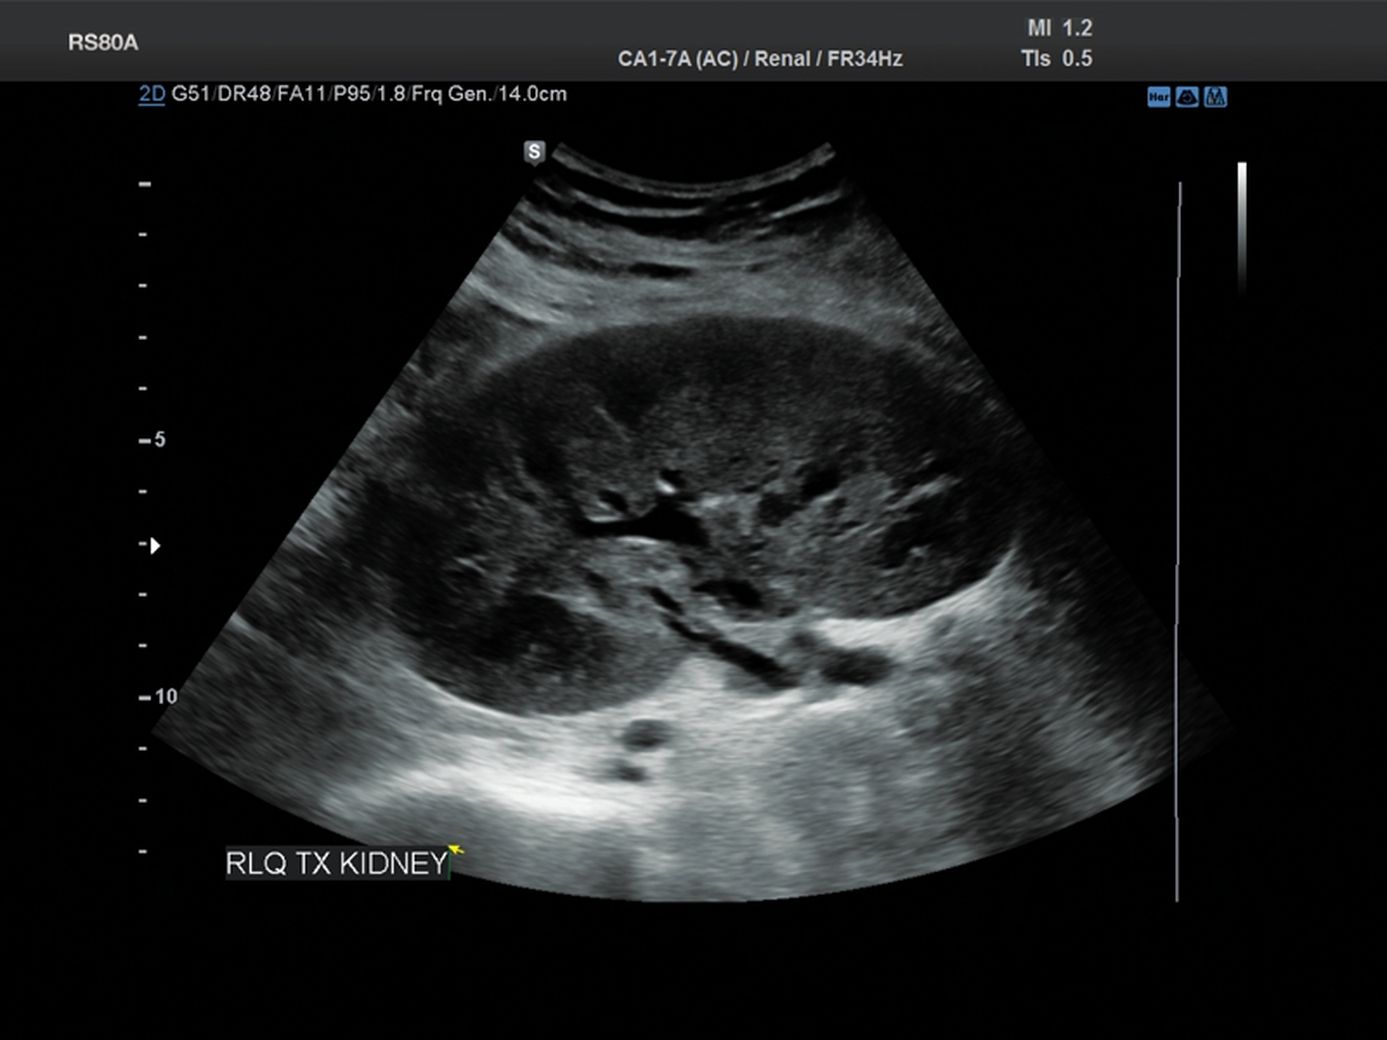

Узи почек в месяц